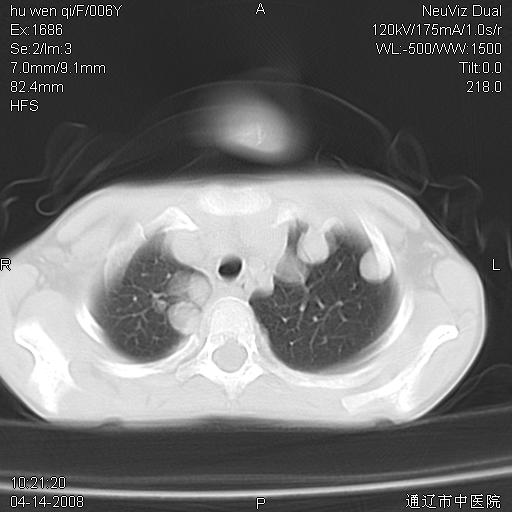

女, 6岁 ,反复咳嗽2周,近两日发热伴右侧胸痛

两肺多发似葡萄状大小不等高密度影,边界清楚,部分见薄壁空洞。左胸壁后方见局限性高密度区,边界清楚,广基与后侧胸壁相连。另示:脾大

考虑:1、金黄色葡萄球肺炎(血源性);

2 肺包囊虫病

3、左侧包裹性积液;

期待结果